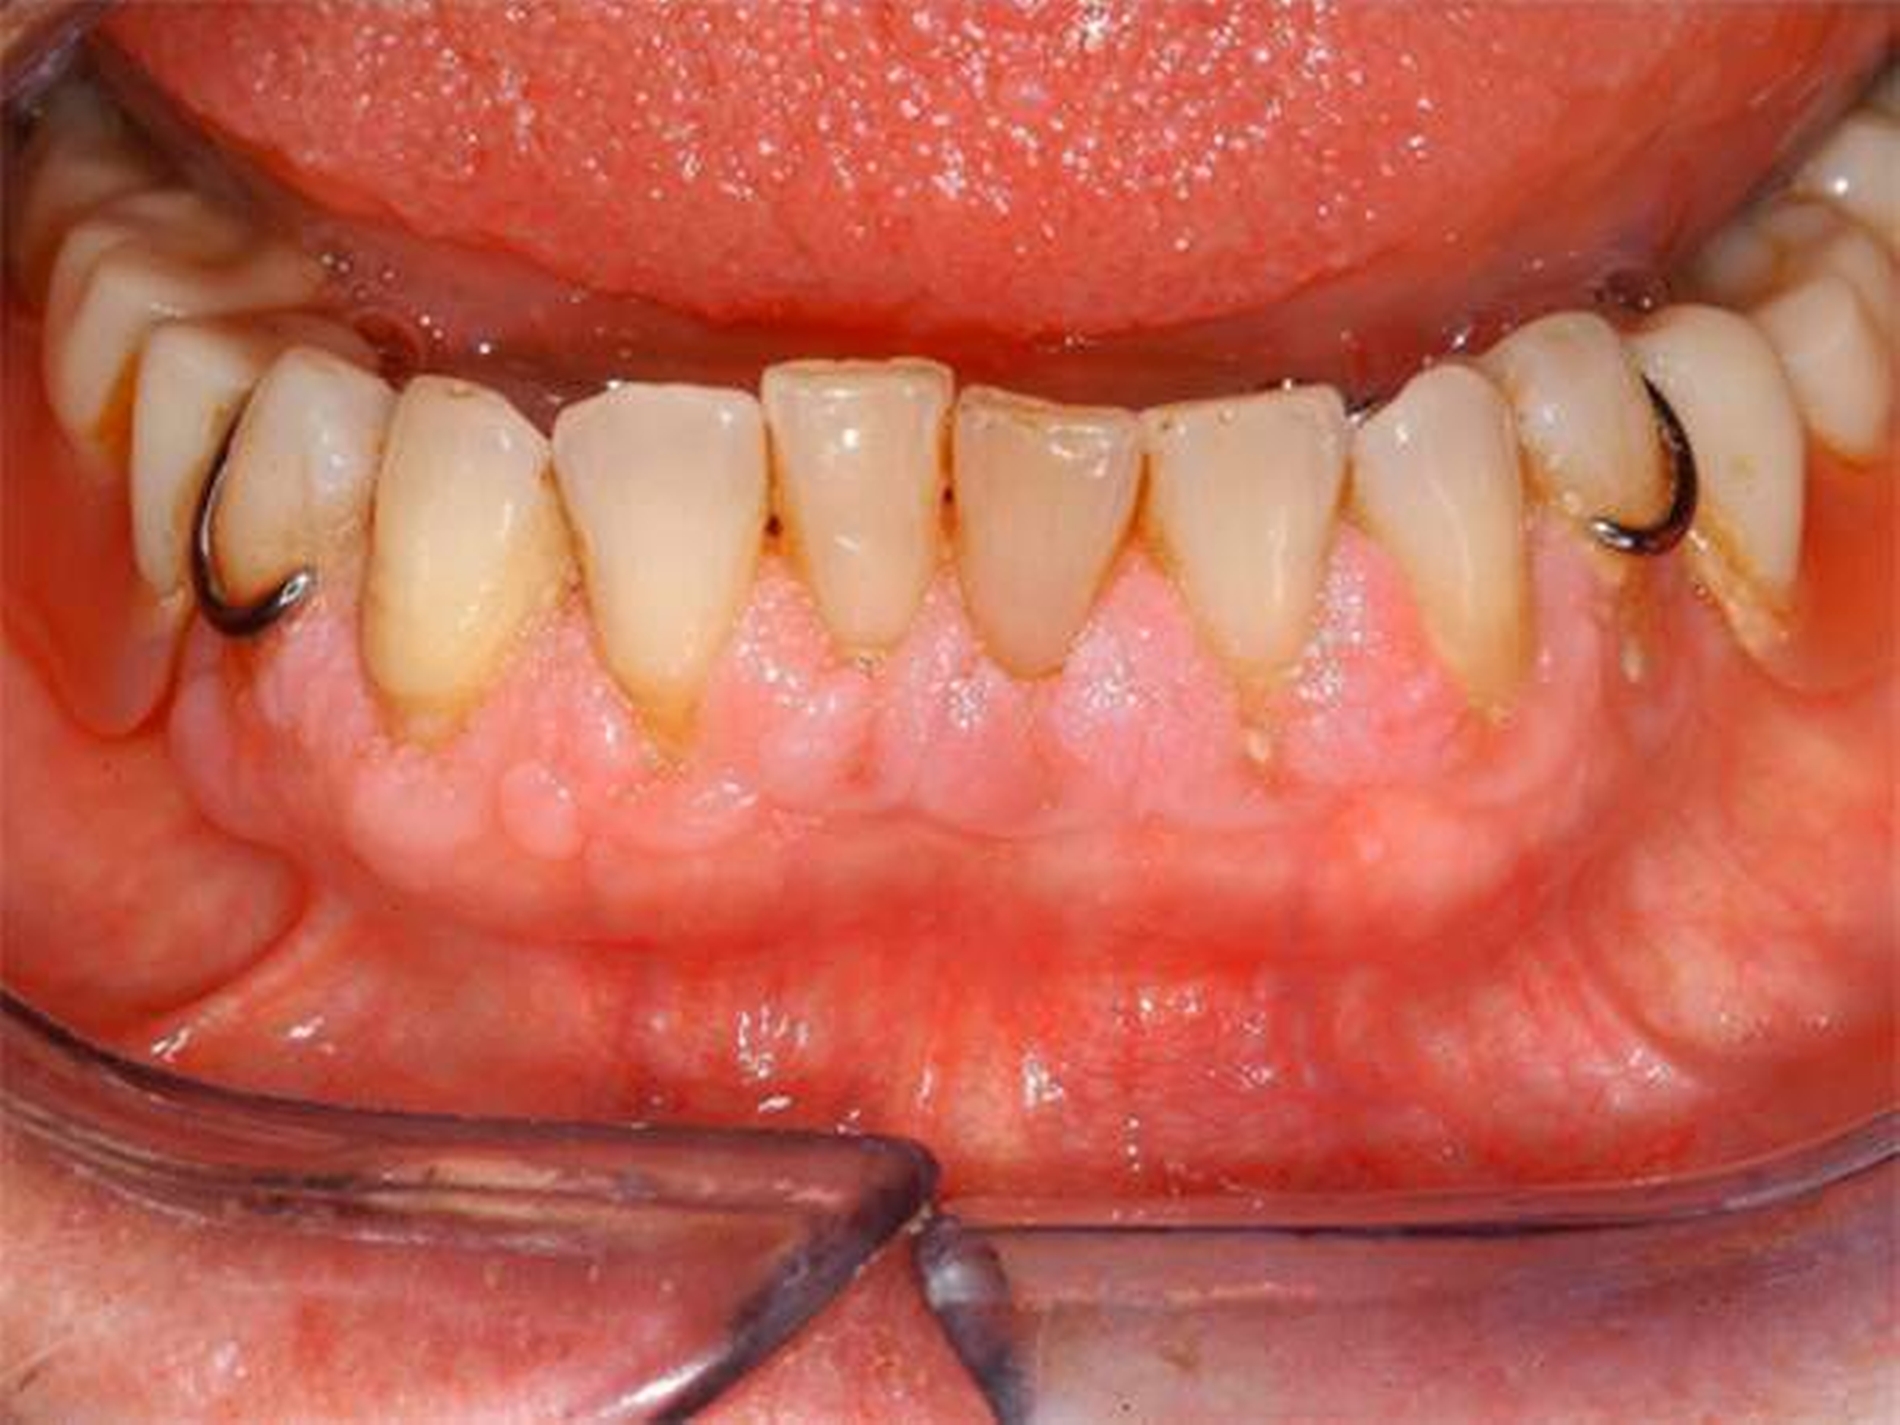

Bei der intraoralen Inspektion zeigte sich eine deutlich hyperplastische Gingiva mit Blutung auf Sondieren (BOP, Abbildungen 1 und 2). Da der Patientin die Handhabung einer Zahnbürste schwerfällt, zeigten sich auch deutliche Plaqueanlagerungen.

Aufgrund der schmerzhaften Gingivitis hatte die Patientin zudem Probleme mit der Nahrungsaufnahme. In der Panoramaschichtaufnahme (Abbildung 3) zeigte sich neben einem impaktierten Eckzahn ein Furkationsbefall der Molaren mit Konkrementen sowie ein altersentsprechender, generalisierter horizontaler Knochenabbau.

Dennoch erschien uns das Volumen der Gingiva nach bereits erfolgter geschlossener Parodontaltherapie ungewöhnlich.